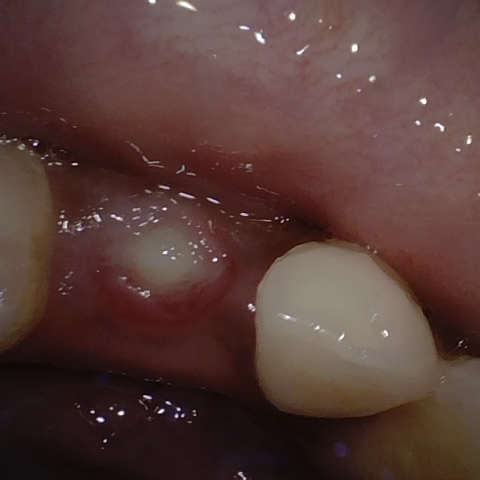

Annotated as "Good"